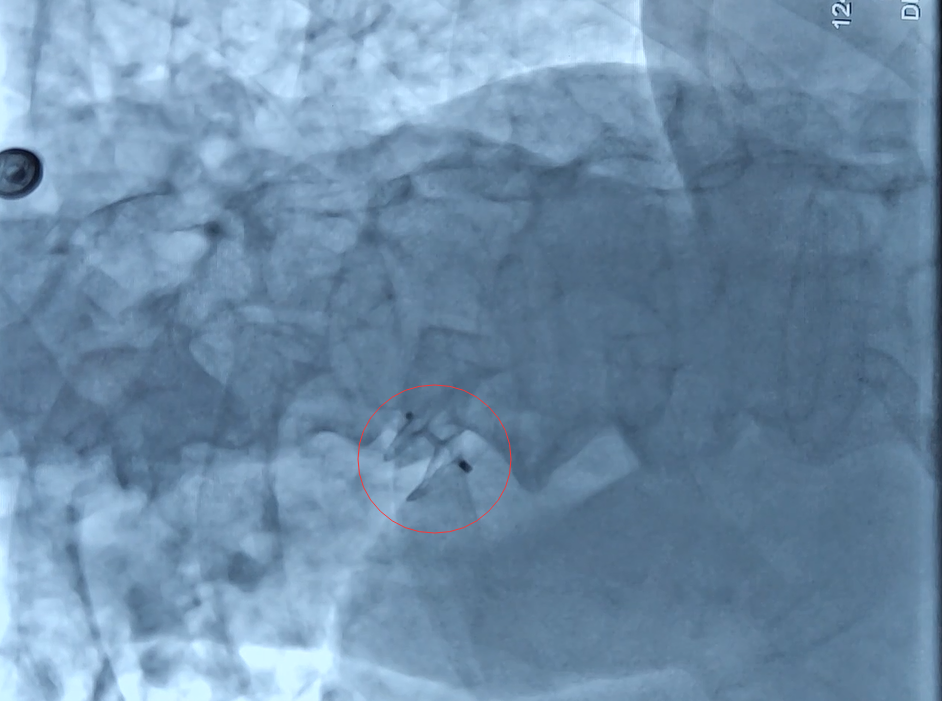

“卵圆孔是左右心房隔膜上的一个小孔,一般在婴儿出生后一年内会自行闭合。若是不闭合,心脏上会留下一个小‘心眼’,称为卵圆孔未闭。”张阳主任科普,“这个小孔会导致心脏血栓容易掉进脑血管,出现体循环栓塞,造成生命危险。”

找到病因,接下来就是对症治疗,为了防止汤先生再次发生脑梗,一劳永逸的解决隐患,上海德济医院心内科张阳主任为汤先生实施了目前新兴的手术治疗方式——“介入封堵术”,从而堵住“心眼”。手术非常顺利,整个过程仅花了30分钟。

(头图中黑色小孔系“多出来的心眼”)